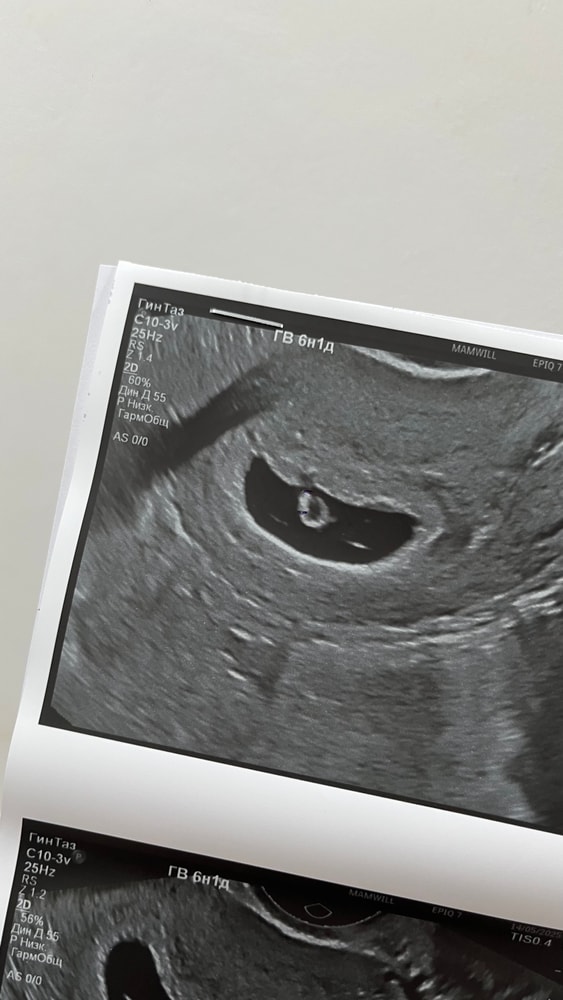

Заключение: маточная беременность 6 недель

Диаметр плодного яйца : 20,8 мм

С эмбрионом, СБ+ ЧСС 160 уд/мин

КТР 3.09 мм

Желточный мешок 4,6 mm